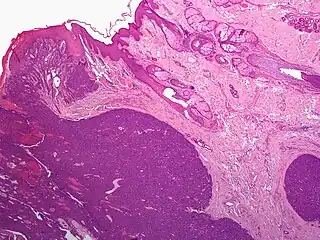

Micrograph showing an acrospiroma. H&E stain.

Hidradenoma refers to a benign adnexal tumor of the apical sweat gland.[1][2] These are 1–3 cm translucent blue cystic nodules. It usually presents as a single, small skin-colored lesion, and may be considered closely related to or a variant of poromas.[3] Hidradenomas are often sub-classified based on subtle histologic differences, for example:[4]